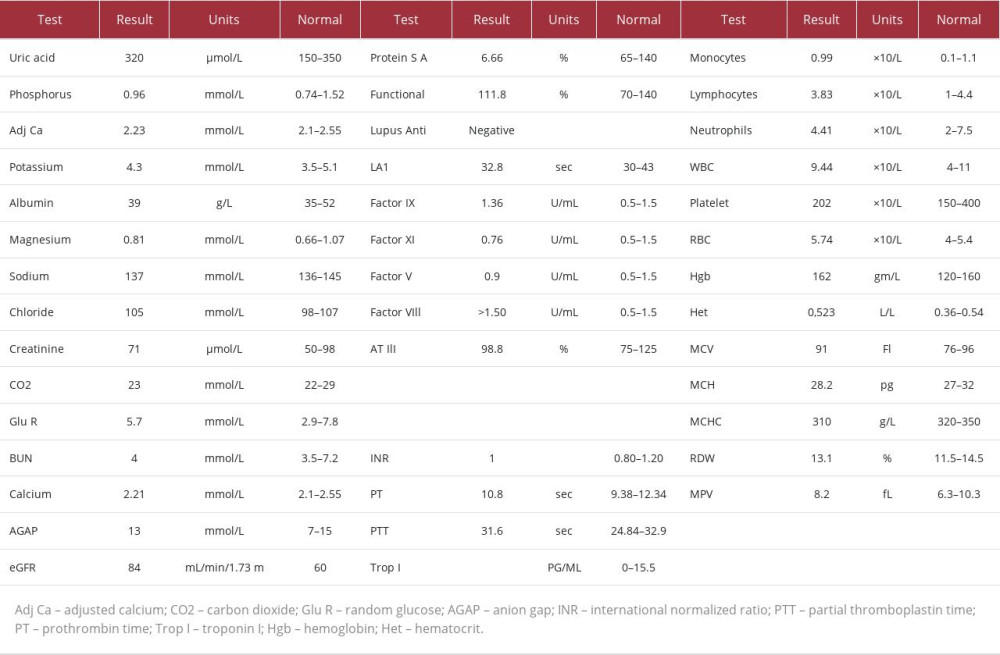

The patient’s laboratory test results (Table 1) were unremarkable. Considering these results, we saw no obvious cause for the weakness, so a point-of-care ultrasound (POCUS) was carried out by an emergency physician. The POCUS showed the possibility of non-compressible veins in the left lower leg. As the patient had a modified Wells score of zero, a D-dimer was measured. Despite the unorthodox presentation, it returned as 1.35, so a DVT ultrasound scan was carried out, which showed thrombi in the left external iliac and common and superficial femoral veins. The left popliteal, posterior tibial, and proximal greater saphenous veins were patent, as shown in Figures 1–3. The patient was admitted to the general ward for observation, and enoxaparin 70 mg twice daily was initiated. Laboratory tests investigating a hypercoagulable state came back negative. Hematology was consulted, and they recommended that the patient be followed in the clinic after repeating the laboratory tests, to follow the course of the illness. After around 10 days, the patient was discharged on apixaban, free of symptoms, including foot drop.